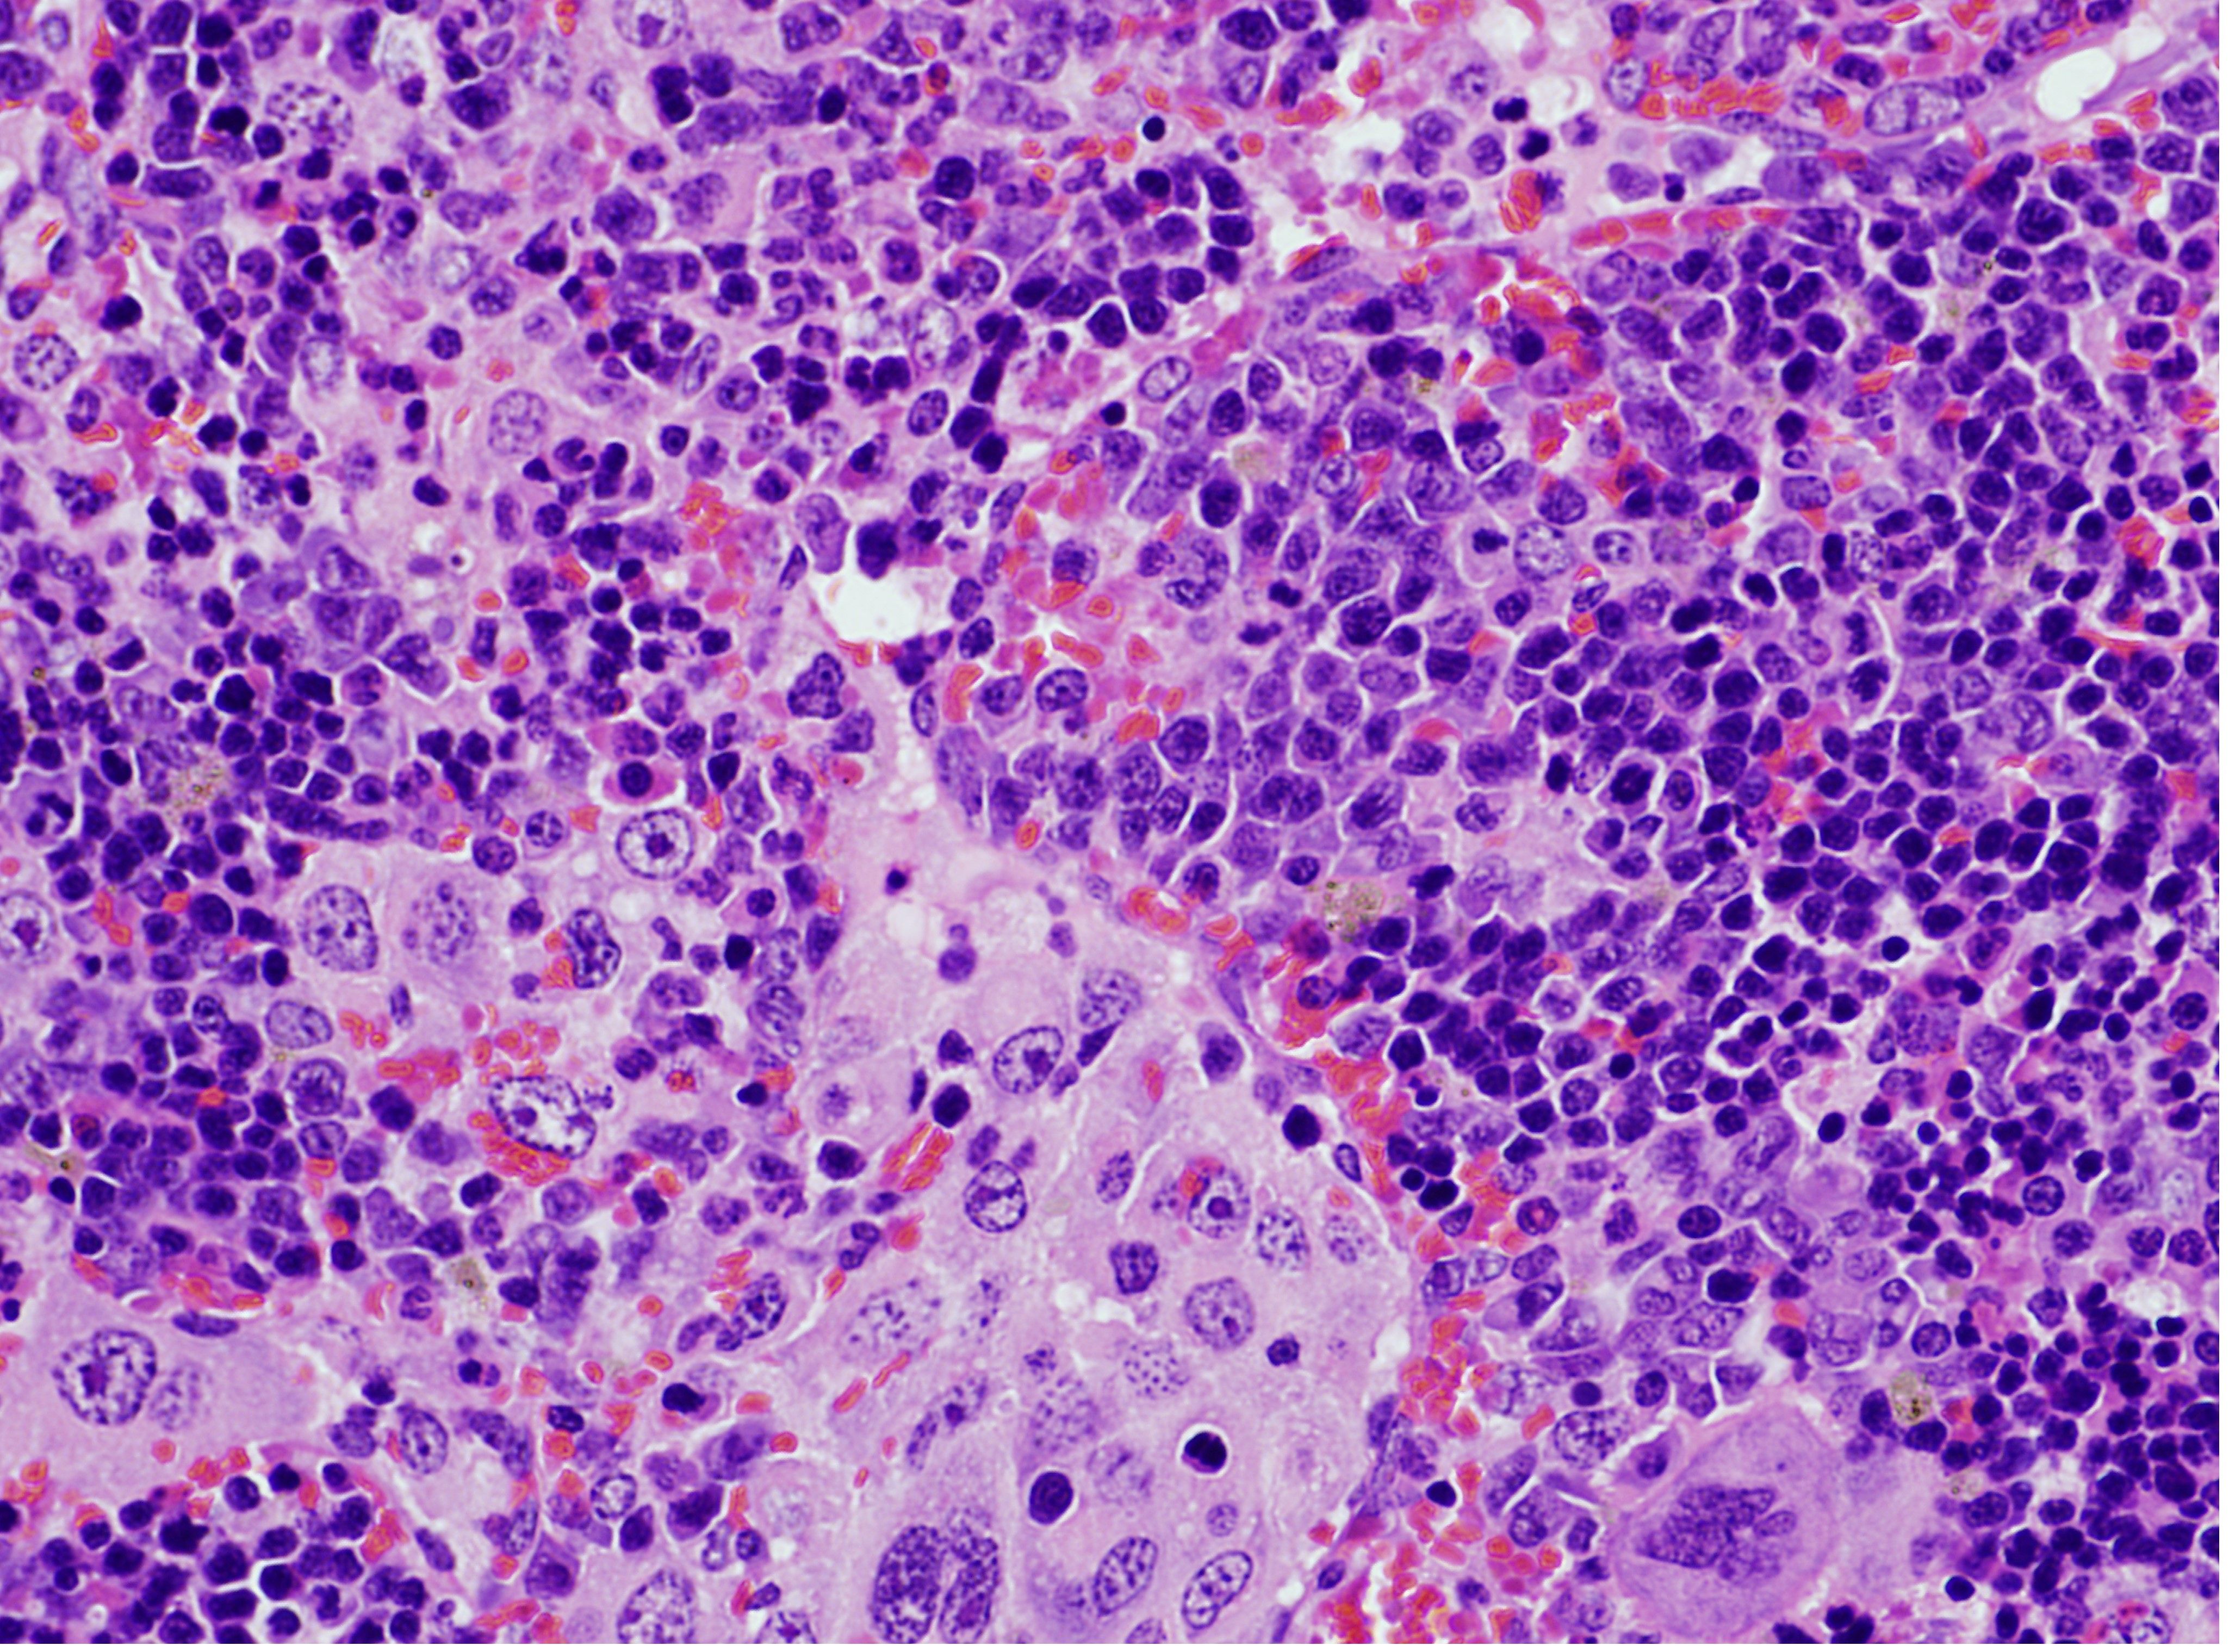

Una alteración genética que afecta al gen VAV1 desempeña un importante papel en tumores derivados de los linfocitos T (linfomas) y el cáncer de pulmón, dos tipos de cánceres que se caracterizan por tener tasas de supervivencia muy bajas, según acaba de revelar un equipo de investigación liderado por el Consejo Superior de Investigaciones Científicas (CSIC).

El trabajo muestra que el espectro de tumores generados depende de la presencia de alteraciones genéticas en otros dos genes distintos (TRP53 y KRAS). A partir de un modelo de ratón modificado genéticamente que contenía la alteración en el gen VAV1, los investigadores han podido determinar el papel de este gen en varios tipos de cáncer. "Por un lado, hemos demostrado que la alteración genética en VAV1 no es suficiente para inducir la formación de tumores en ningún órgano de los ratones. Sin embargo, cuando se combina con la eliminación del gen antitumoral TRP53 provoca el rápido desarrollo de un tumor muy específico de linfocitos T conocido con el nombre de linfoma periférico de células T. Pero no se han detectado otros tipos tumorales, indicando que la combinación de estas dos alteraciones genéticas solo da lugar a un tipo de tumor", según especifica Robles-Valero.